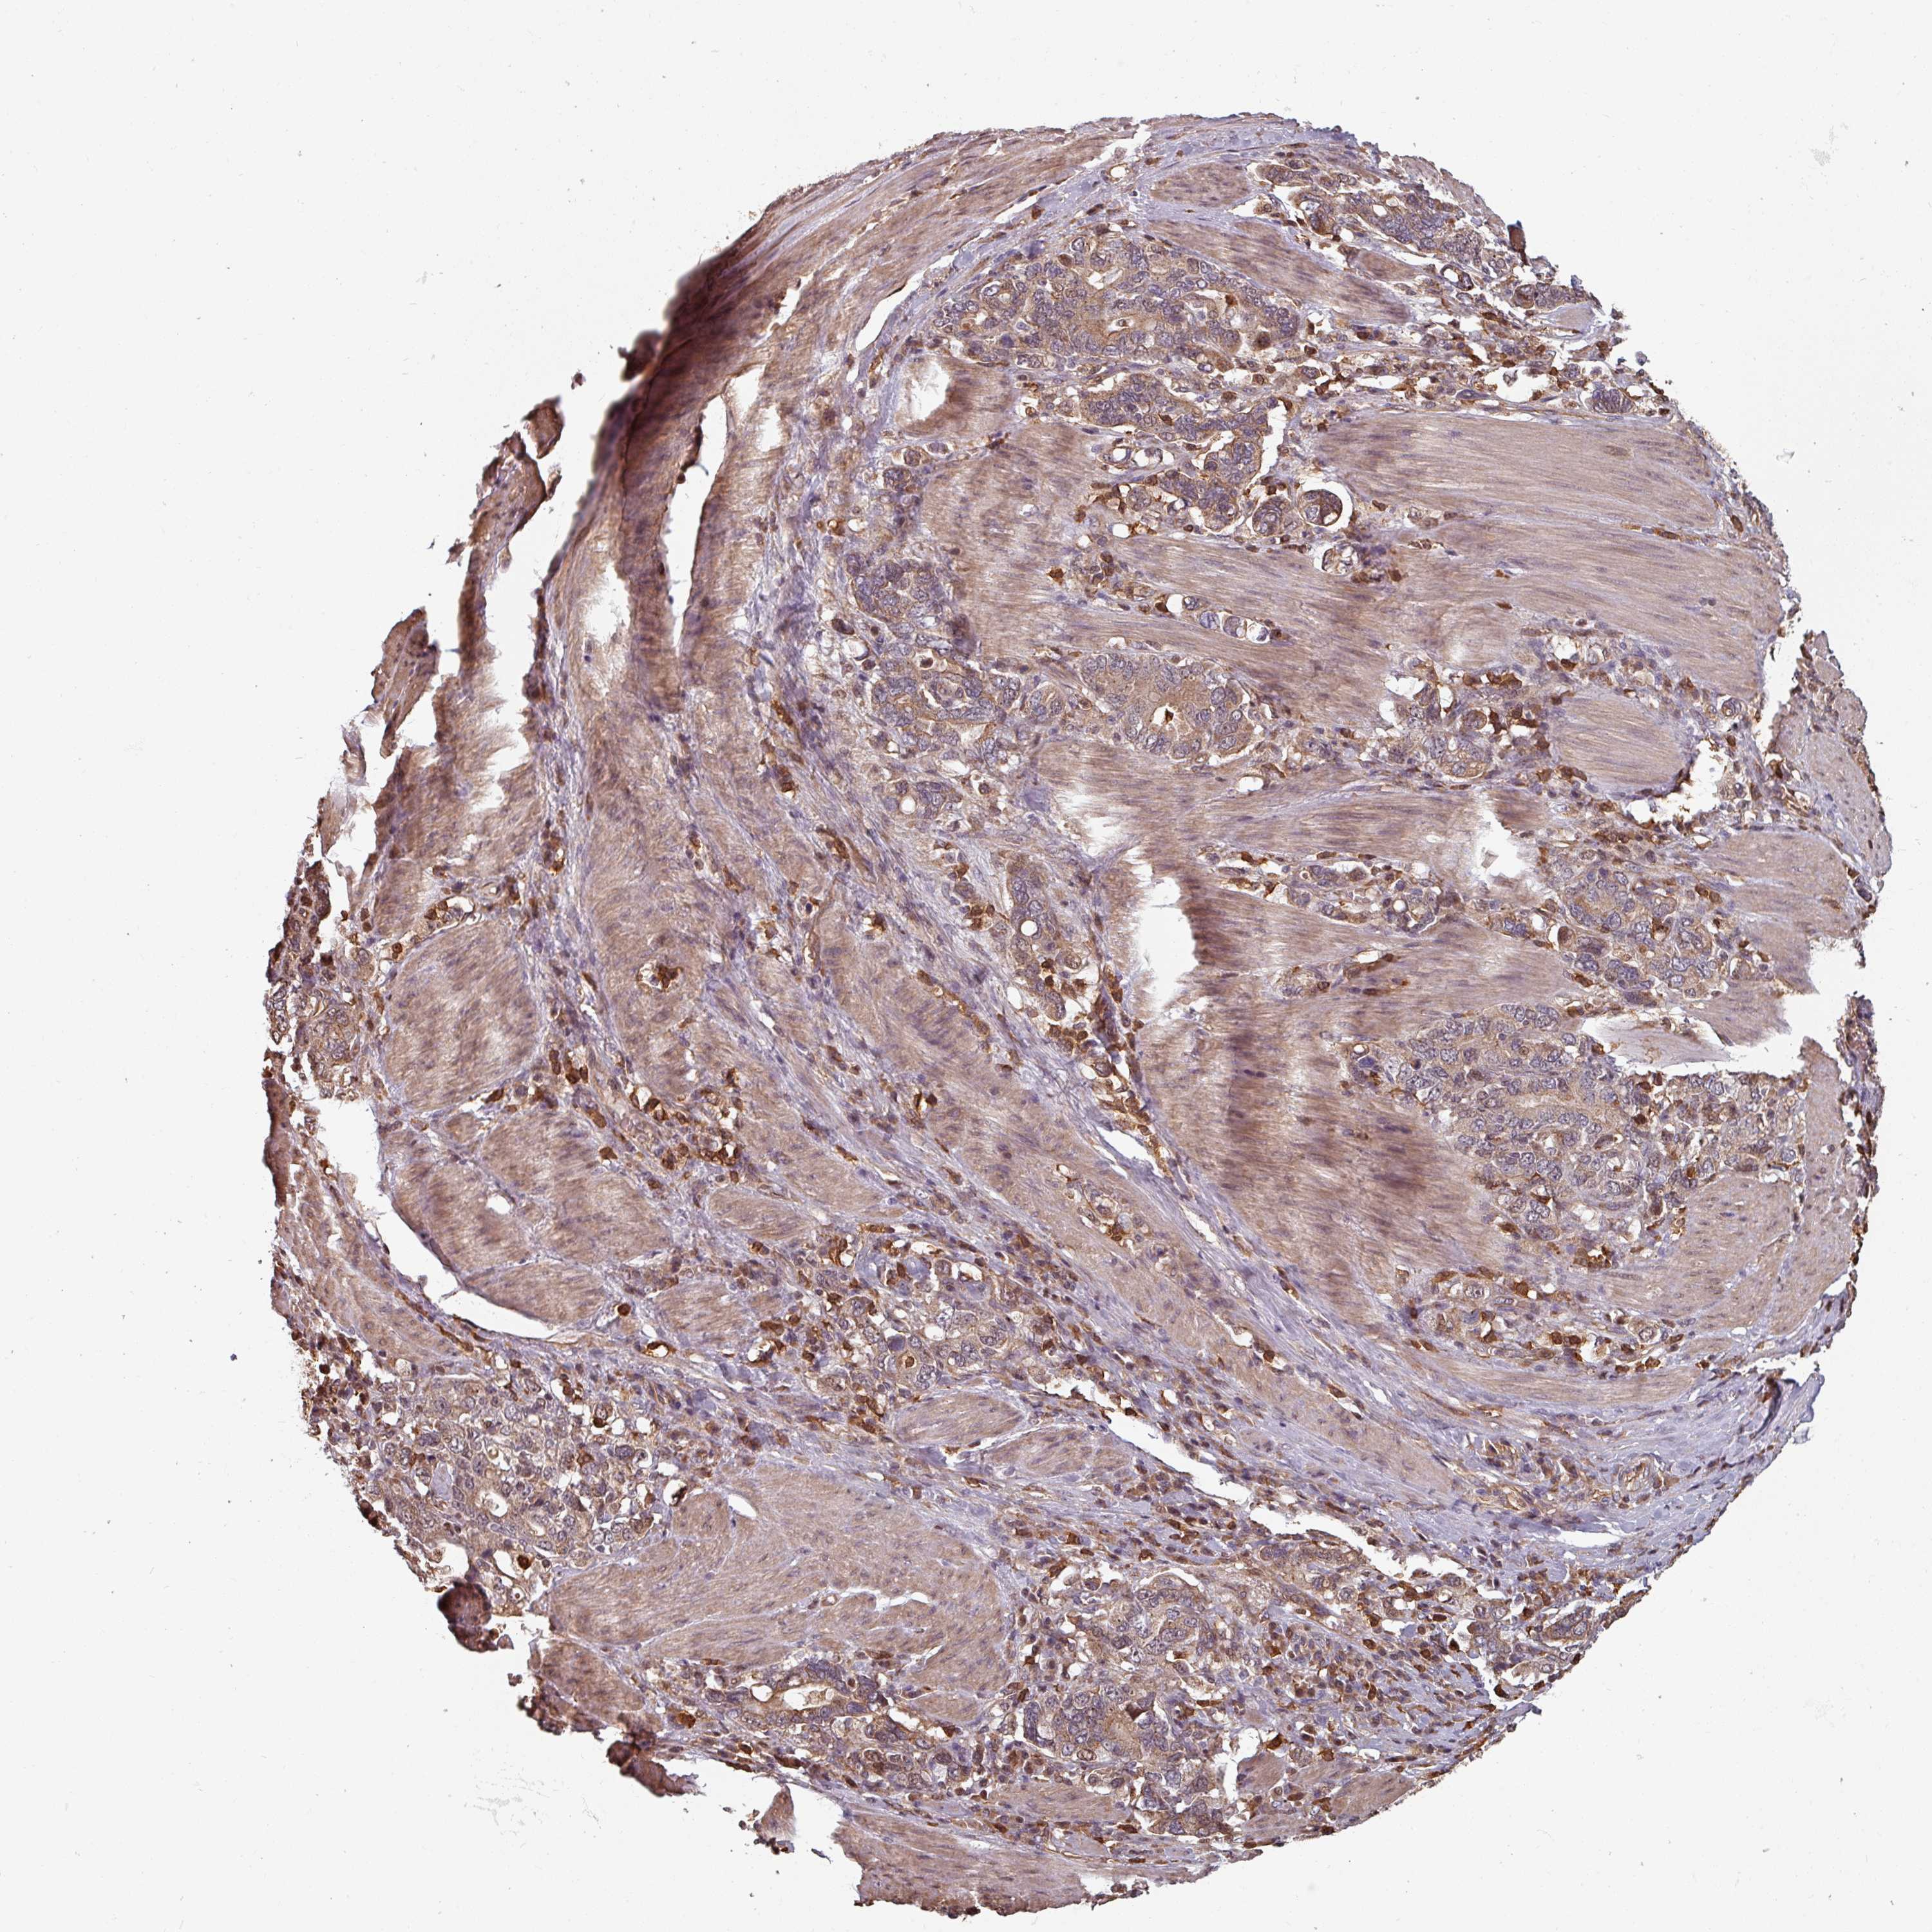

STOMACH CANCER - Protein expressioni

A mouse-over function shows sample information and annotation data. Click on an image to view it in a full screen mode. Samples can be filtered based on level of antibody staining by selecting one or several of the following categories: high, medium, low and not detected. The assay and annotation is described here.

Note that samples used for immunohistochemistry by the Human Protein Atlas do not correspond to samples in the TCGA dataset.

Antibody stainingi

Antibody staining in the annotated cell types in the current human tissue is reported as not detected, low, medium, or high, based on conventional immunohistochemistry profiling in selected tissues. This score is based on the combination of the staining intensity and fraction of stained cells.

Each image is clickable and will lead to virtual microscopy that enables deeper exploration of all samples and also displays staining intensity scores, fraction scores and subcellular localization as well as patient and tissue information for each sample.

Antibody HPA051122

Staining

High

Medium

Low

Not detected

Intensity

Strong

Moderate

Weak

Negative

Quantity

>75%

75%-25%

<25%

None

Location

Nuclear

Cytoplasmic/membranous

Cytoplasmic/membranous,nuclear

Adenocarcinoma, NOS